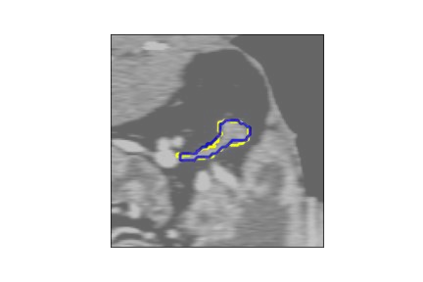

The human annotations are imperfect, especially when produced by junior practitioners. Multi-expert consensus is usually regarded as golden standard, while this annotation protocol is too expensive to implement in many real-world projects. In this study, we propose a method to refine human annotation, named Neural Annotation Refinement (NeAR). It is based on a learnable implicit function, which decodes a latent vector into represented shape. By integrating the appearance as an input of implicit functions, the appearance-aware NeAR fixes the annotation artefacts. Our method is demonstrated on the application of adrenal gland analysis. We first show that the NeAR can repair distorted golden standards on a public adrenal gland segmentation dataset. Besides, we develop a new Adrenal gLand ANalysis (ALAN) dataset with the proposed NeAR, where each case consists of a 3D shape of adrenal gland and its diagnosis label (normal vs. abnormal) assigned by experts. We show that models trained on the shapes repaired by the NeAR can diagnose adrenal glands better than the original ones. The ALAN dataset will be open-source, with 1,594 shapes for adrenal gland diagnosis, which serves as a new benchmark for medical shape analysis. Code and dataset are available at https://github.com/M3DV/NeAR.